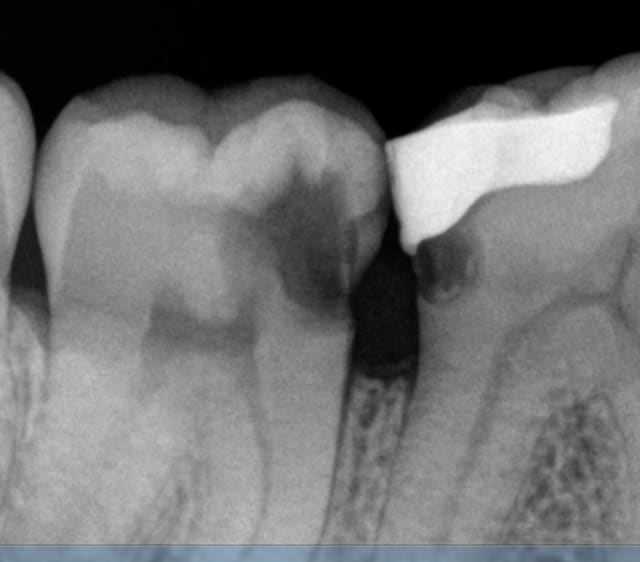

Et c'est reparti ce matin de plus belle : pulpite. L'embarras du choix -))))

C'est pas comme si on faisait des radios de controle régulièrement hein ? -))))

Capture d e cran 2015 11 30 09.34 - Eugenol